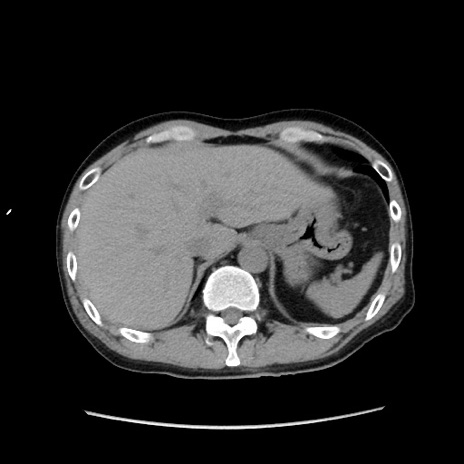

症例37(横断像)

【症例】40歳代 男性

【主訴】腹痛

【現病歴】4時間ほど前に電車に乗車中に臍部上より腹痛出現。徐々に増悪し起立困難となり、救急外来受診。生ものは数日食べていない。今朝お雑煮を食べた。

【身体所見】BT 36.8℃、BP 117/84mmHg、HR 91/min、SpO2 97%、苦悶様、腹部:臍上部広範囲圧痛あり、反跳痛±

【データ】WBC 8100、CRP 0.03